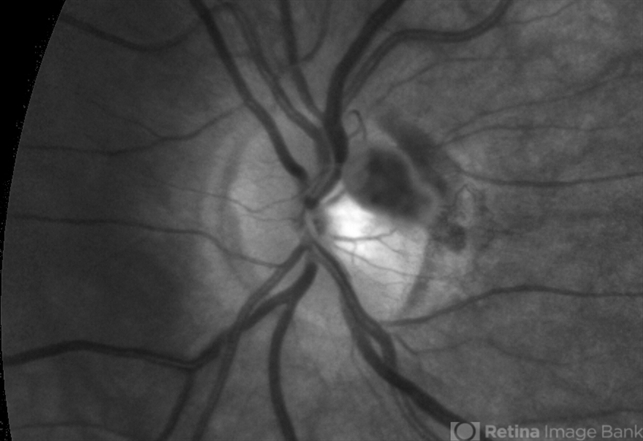

- Unusual presentation of VHL juxtapapillary hemangioblastoma detached from retina with feeder vessels

- Von Hippel-Lindau, retinal hemangioblastoma

- 30-year-old female with fhx VHL and CNS hemangioblastomas and visceral lesions. P/C with a floater (no PVD or VH) after episodes of vomiting.